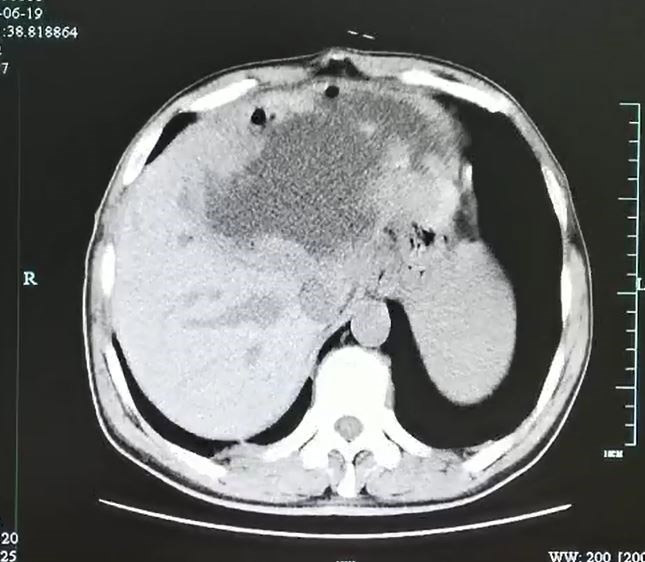

ภายหลังจากแพทย์ตรวจเช็กร่างกายอย่างละเอียด ก็พบว่า ตับของคนไข้มีถุงหนองขนาดใหญ่ ความยาว 7.5 นิ้ว และลึก 4.7 นิ้ว และสุดท้ายก็จำเป็นต้องตัดตับที่เสียหายของคนไข้ทิ้งไปถึงครึ่งหนึ่ง หลังจากพบว่ามีการติดเชื้อ และจากตรวจสอบในขั้นต่อมา ทำให้แพทย์ต่างตะลึงไม่น้อย เมื่อพบว่าภายในรูที่มีไข่จำนวนนับไม่ถ้วน เป็นของพยาธิใบไม้ตับ ซึ่งมีสาเหตุมาจากการกินอาหารที่ไม่ผ่านการปรุงสุก